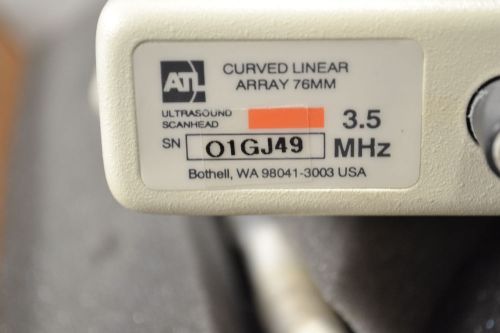

ATL 3.5 MHz Curved Linear Array Probe, 76mm (L2)